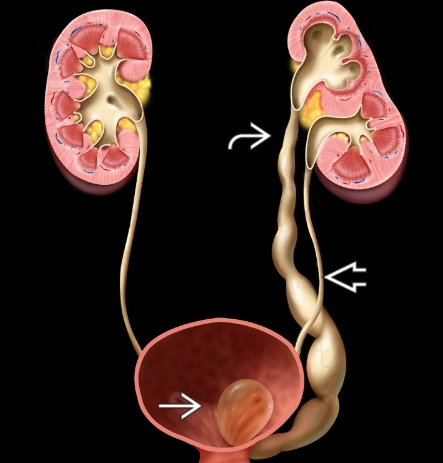

Niệu quản đôi (Ureteral duplication)

Niệu quản chẻ đôi (Bifid ureter)

Niệu quản lạc chỗ (Ectopic ureter)

Sa lồi niệu quản (Ureterocele)